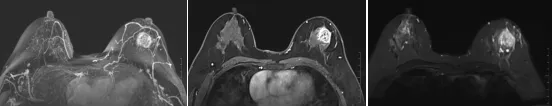

乳腺MRI,借助强大磁场、无线电波及计算机技术,对乳腺进行成像的检查方法。它就像一个“高清雷达”,扫描出乳腺的内部情况,清晰显示出乳腺的大小、形态、腺体组织和病灶的细节,帮助发现隐藏的微小病变,为临床诊断提供全面信息。

分辨率高:能发现超声、钼靶看不到的微小病灶,避免漏诊。

诊断精准:能清晰区分病灶良恶性,为治疗提供可靠依据。

乳腺MRI之所以被医生推荐,核心优势很突出,和超声、钼靶形成互补,三者结合才能实现最精准的乳腺筛查。